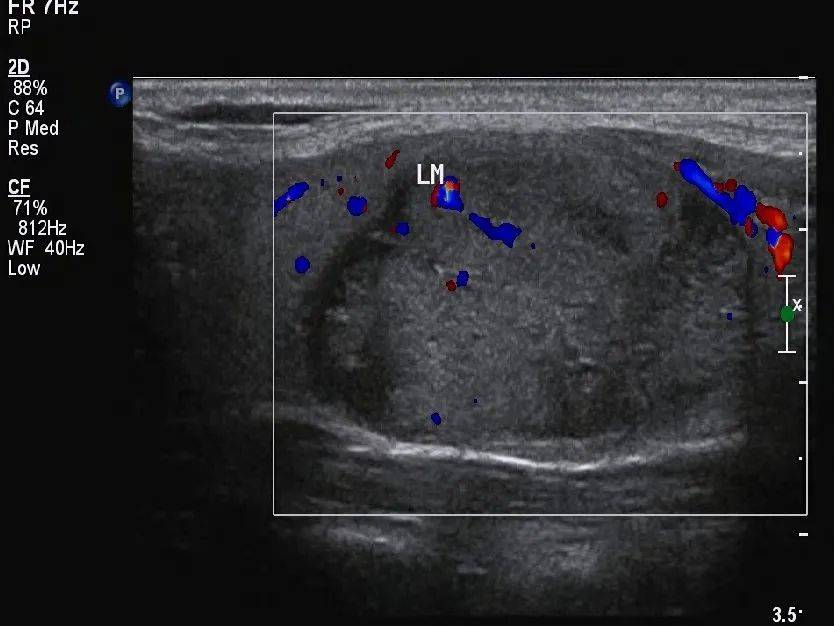

甲状腺形态失常,左侧叶增大,内部回声不均匀,见囊实混合性结节,大小约 33mm×19mm×28mm ,形态规则,边界清,纵横比 <1 ,内部以实性为主,实性部分见少许散在点状强回声(图 1 、图 2 ),结节周边伴低回声声晕,声晕厚度不均匀(图 3 ), CDFI:结节周边见环绕血流信号,内部见不规则分布的血流信号,局部较丰富(图 4 、图 5 )。SMI:结节局部微细血流信号丰富(图 6 )。

图 3 CDFI 显示周边有半环状血流绕行